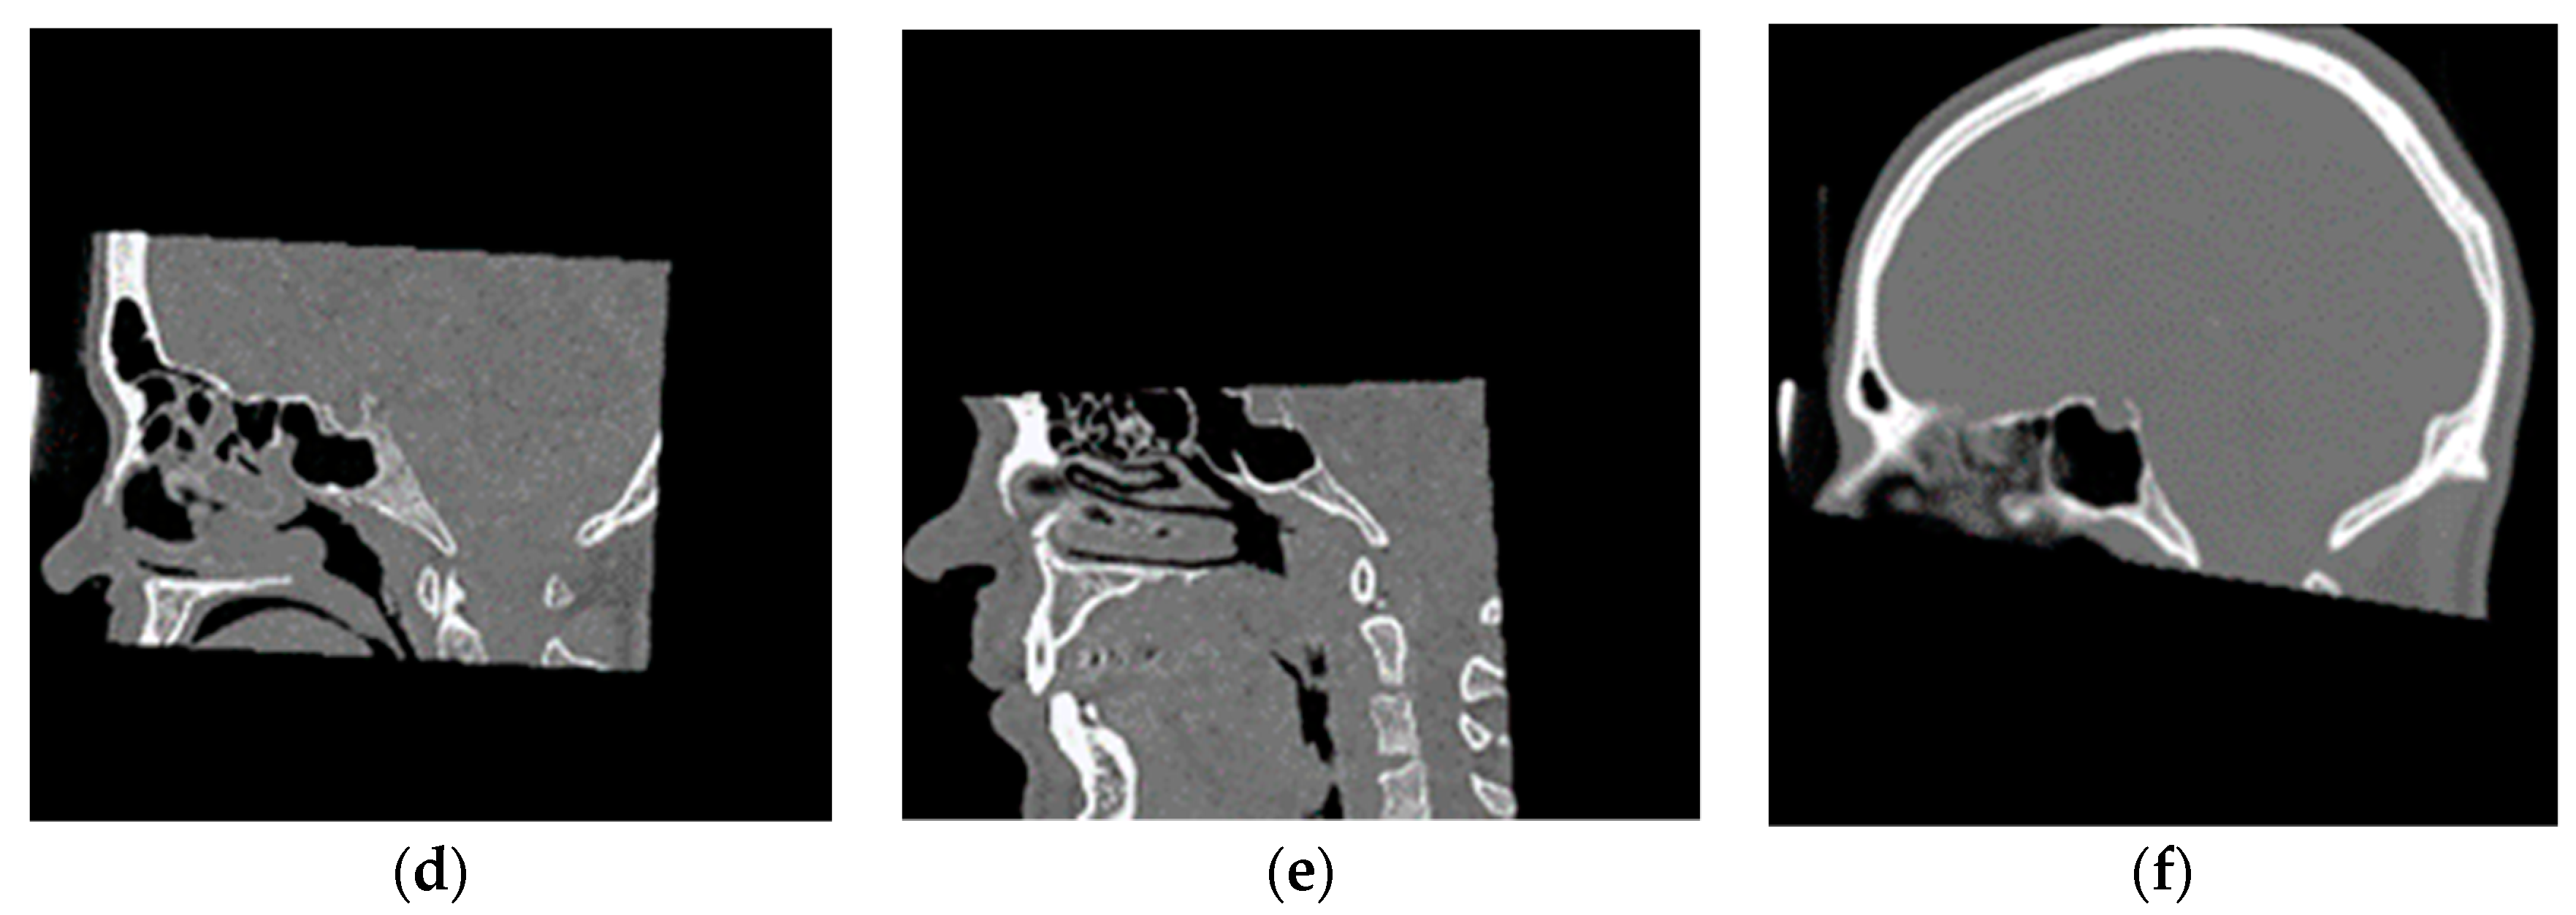

2.2.1. Training Dataset

2.2.2. Validation Dataset